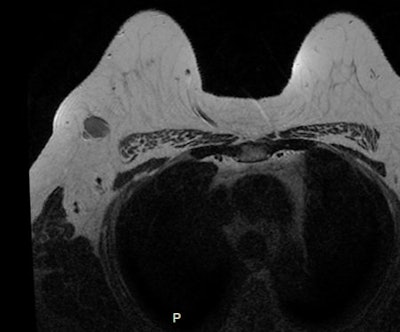

Invasive ductal carcinoma with positive axillary lymphadenopathy. The detection of malignant masses is relatively easy using DWI for both index tumor and axillary positive lymph node. ADC values of the index tumor and positive homolateral lymph node were less than 0.9. This case illustrates the usefulness of DWI to detect both index tumor and positive lymphadenopathy. Images courtesy of Dr. Isabelle Thomassin-Naggara.